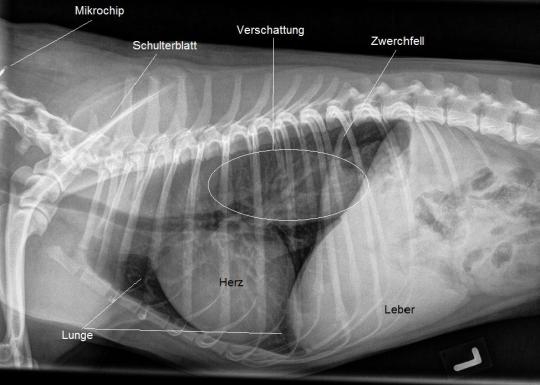

Ein Röntgen des Bauches wird angefertigt, welches unauffällig ausfällt - allerdings ist dafür im noch knapp abgebildeten Brustbereich eine Verdichtung ("Weissfärbung" der oberen/hinteren Lungenanteile) bemerkt. Ein Bruströntgen bestätigt diesen Befund.

Das Bruströngen ist verdächtig für eine Erweiterung der Speiseröhre in diesem Bereich. Zur weiteren Abklärung erhält Jago nun Futter, welches mit einem Röntgenkontrastmittel vermischt ist. In einer weiteren Röntgenaufnahme wird dann dokumentiert, dass das geschluckte Futter nicht ordnungsgemäss im Magen gelandet ist, sondern in der stark erweiterten Speiseröhre in der Brusthöhle liegen geblieben ist - der Hund leidet unter einem Megaösophagus.